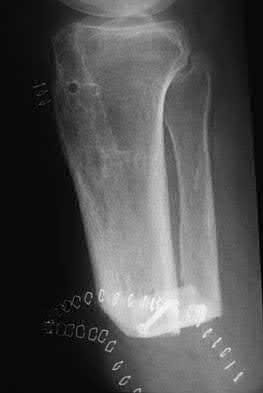

A 25-year-old female is involved in a motor vehicle collision. She presents with the isolated injury seen in Figures A through D. Her leg is swollen but her skin is intact. She has no clinical signs of compartment syndrome. Which of the following treatment options will allow for maintenance of fracture alignment and minimize the risk of soft tissue complications?

The patient presents with a closed distal third metaphyseal-diaphyseal distal tibia fracture with simple intra-articular extension. Immediate intramedullary nailing along with percutaneous fixation of the articular component provides appropriate restoration of length, rotation and alignment and minimizes the risk of wound complication.

Displaced distal third tibia fractures may be associated with simple intraarticular extension. Operative treatment of intra-articular distal tibia fractures has historically been performed with open reduction and internal fixation. Early open reduction and plate fixation of pilon fractures has been associated with high rates of infection and wound complication. In select patterns with simple articular extension, percutaneous screw fixation and medullary nailing may provide appropriate reduction with minimal soft-tissue risk.

Figures A and B demonstrate a distal third tibial shaft fracture with simple intra-articular extension. The axial and coronal CT cuts in Figures C and D further clarify the articular injury. Illustrations A and B demonstrate a comminuted distal third tibial fracture with simple intra-articular extension. Illustrations C and D are fluoroscopic images of the same injury after intramedullary nailing and percutaneous fixation of the articular component.